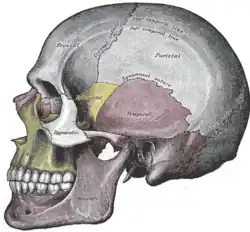

Etmoide visível no centro (dentro da órbita ocular). Vista lateral do crânio.

Vista lateral do crânio. Crânio de frente.